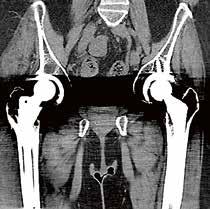

Metallartefaktreduktion serienmäßig

Mit SEMAR, der iterativen Metallartefaktreduzierung, können sogar schwierige Untersuchungen, z. B. mit Zahnfüllungen, Wirbelsäulenimplantaten, beidseitigen Hüftimplantaten, NeuroCoils und Schrittmachern durch einen flexiblen und reibungslosen Arbeitsablauf sicher ausgewertet werden. Der Single­Energy­Metall­Artefakt­Reduktionsalgorithmus beinhaltet zwei erfolgreiche Ansätze zur Reduzierung von Metallartefakten: Er kombiniert eine Strahlaufhärtungskorrektur mit dem Iterations­Hybridverfahren AIDR 3D Enhanced, um die Rauschtextur und scharfe Details neben Metallen wiederherzustellen. Dieser Prozess wird Schicht für Schicht über den gesamten Untersuchungsbereich durchgeführt, was in kürzester Zeit zu einem Artefaktfreien diagnostischen Bildstapel führt. SEMAR kann sowohl in schon hinterlegten, standardisierten Protokollen genutzt oder alternativ im Postprocessing über die Rohdaten ausgewählt und angewendet werden.

Die SEMAR-Metallartefaktreduktion minimiert die durch Implantate verursachten Bildstörungen und sichert so die Diagnostik sowohl des Metalls selbst wie auch des umliegenden Gewebes.

Dr. Thomas Bayer: Mit dem Adora System können wir die Aufnahmerichtung der Bildgebung jederzeit optimal einstellen, ohne den Patienten umlagern zu müssen, wie beispielsweise bei axialen Aufnahmen beider Hüftgelenke. Kraftsparende Arbeitsabläufe, eine durchdachte Menüführung und um­

59-jähriger männlicher Patient mit Z.n. periprothetischer Fraktur nach Hüft-TEP; Abb. links: Oberschenkelaufnahme in Stitching-Technik zur präoperativen Planung, Abb. rechts: Post-OP-Dokumentation.